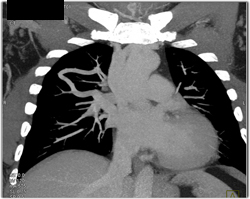

Diagnosis

Pulmonary Arteriovenous Malformation (PAVM)